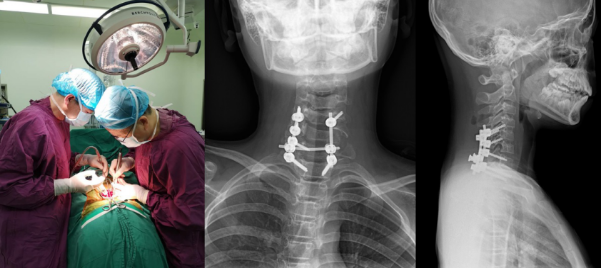

湘雅三医院脊柱外科邓幼⽂教授、臧晓方教授、王剑龙教授、王卫国主治医师,及神经外科王知非教授、吴光勇副教授、颜辉主治医师等,联合肿瘤科专家、医学影像专家迅速启动MDT诊治模式,对患者的病情进⾏了详细的评估。通过完善增强三维CT、增强核磁共振、数字化3D肿瘤模型,彻底摸清肿瘤和周围神经、血管、骨骼的毗邻关系,制定了详尽而周密的⼿术计划——完整切除肿瘤并防止误伤颈部神经血管。

脊柱外科主任邓幼文教授和神经外科主任王知非教授联袂主刀,历时6小时成功将这枚颈部“炸弹”成功拆除,颈部神经毫发无伤。术后一周,患者肌力感觉基本恢复正常,已下地行走。